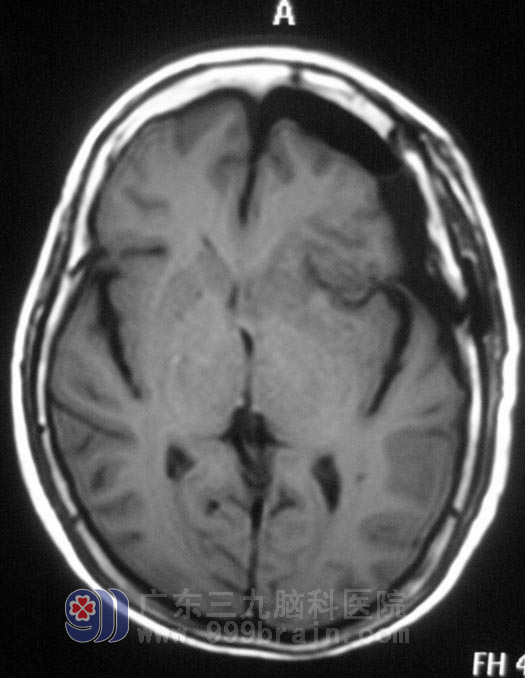

偏偏在半个月前,李女士又出现了间歇性头晕;一周前,头晕症状加重,伴有头痛。当地医院行头颅MR检查提示左侧蝶骨嵴占位性病变,考虑脑膜瘤。真是祸不单行。

在广东三九脑科医院住院后,经过全面检查及评估,李女士各项功能均可接受手术治疗。2月1日,由综合神经外科 鲁明主任主刀,在全麻下行左侧蝶骨嵴脑膜瘤切除术+颅内压探头植入术,术中见颅骨及硬膜血供丰富,肿瘤呈粉红色,质硬,包膜完整,广基与蝶骨嵴中外1/3硬膜相连,在显微镜下分块全切肿瘤,手术过程顺利。手术后没有出现并发症,已康复办理出院。术后病理结果为:合体型脑膜瘤。